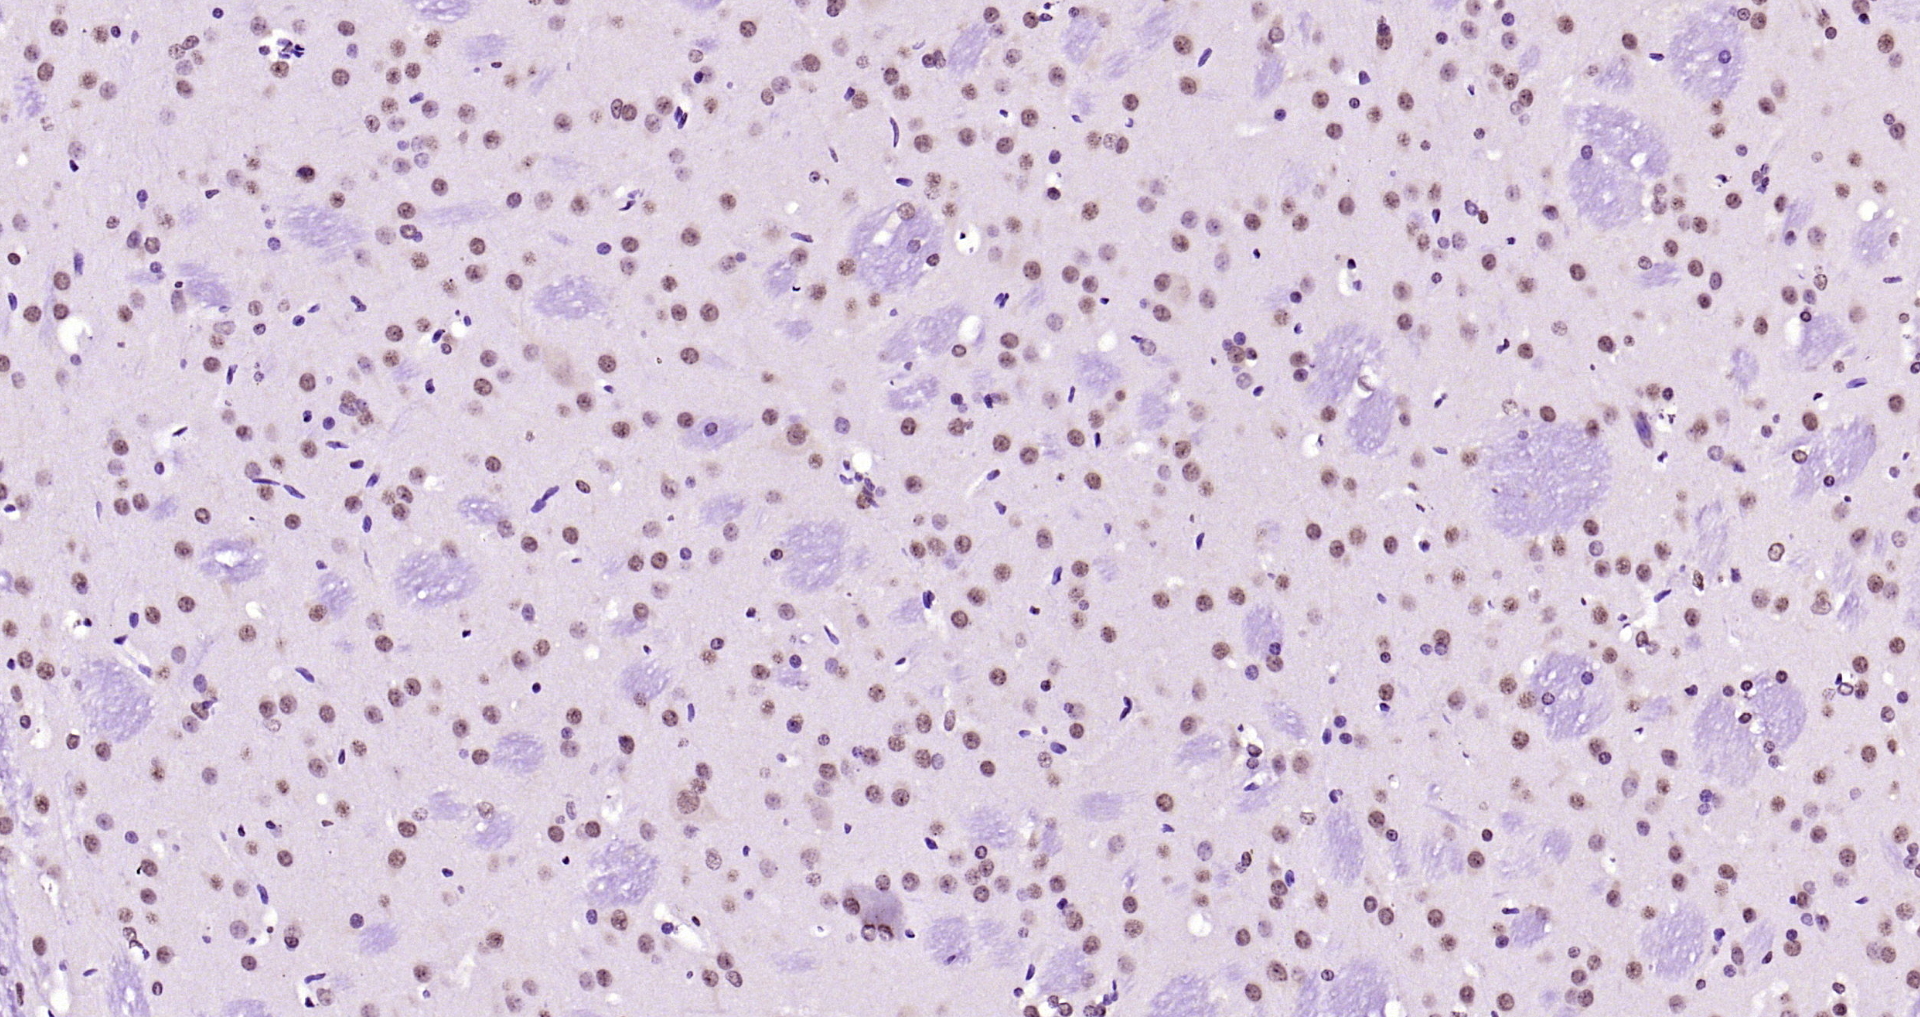

Paraformaldehyde-fixed, paraffin embedded Human colon cancer; Antigen retrieval by boiling in sodium citrate buffer (pH6.0) for 15min; Block endogenous peroxidase by 3% hydrogen peroxide for 20 minutes; Blocking buffer (normal goat serum) at 37°C for 30min; Antibody incubation with SOX9 Polyclonal Antibody, Unconjugated (bs-10725R) at 1:400 overnight at 4°C, DAB staining.